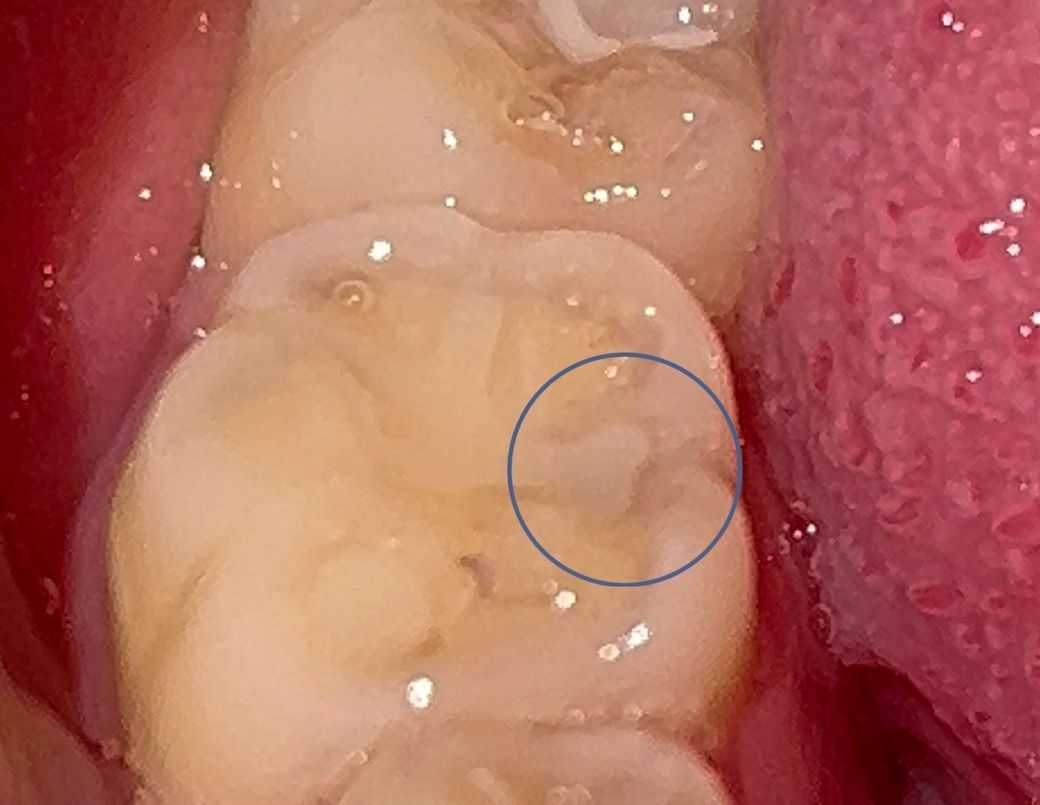

이거 충치 심한가요?? ㅠㅠ 도와주세요

이거 충치인거는 알겠는데 동그라미 친 부분이 회색이에요 범위는 작은데 걱정되네요 레진으로 될까요..? ㅠㅠ 심한건가요?? ㅠ

충치는 아닐꺼 같습니다. 약간 착색이 발생한거 같고 정확한건 치과에 가셔서 엑스레이를 찍어보시고 검진을 해봐야 알수 잇을것같습니다.

내부 충치가 의심되지만 그 크기는 위 사진보다는 엑스레이를 통해서 판단이 가능한 부분입니다.

엑스레이 사진이 있어야 정확한 판단이 가능합니다 평소 증상은 어땠는지도 중요합니다 뜨거운 음식 등에 민감하게 반응했다면 깊은 이차충치일 수 있습니다

회색으로 보이는 부분은 충치가 진행되었을 가능성이 있으며, 충치 깊이정도에 따라 레진 가능여부가 달라지게 됩니다. 만약 충치가 얕은 경우에는 충치를 제거후 레진으로 떼우는 것이 가능하나, 만약 깊은 경우에는 인레이나 크라운 치료가 필요로 될수 있습니다.

따라서 보다 정확한 상태 확인을 위해 치과에 가서 정확한 상태를 확인하고 치료를 받길 권합니다.